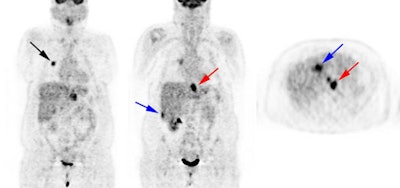

Esophageal carcinoma: The patient shown below presented with a history of progressive dysphagia. A barium swallow revealed a distal esophageal mass. CT and FDG PET imaging were performed for patient staging. The large esophageal mass (white arrows on CT) demonstrated intense tracer uptake (black arrows on PET scan). Uptake could also be seen in regional gastrohepatic ligament nodal metastases (right images). Retrocrural metastases seen on CT blended imperceptibly with the primary tumor on PET imaging. The was no evidence of distant metastatic disease. (Click here to view rotating volume image [1.5 MB])